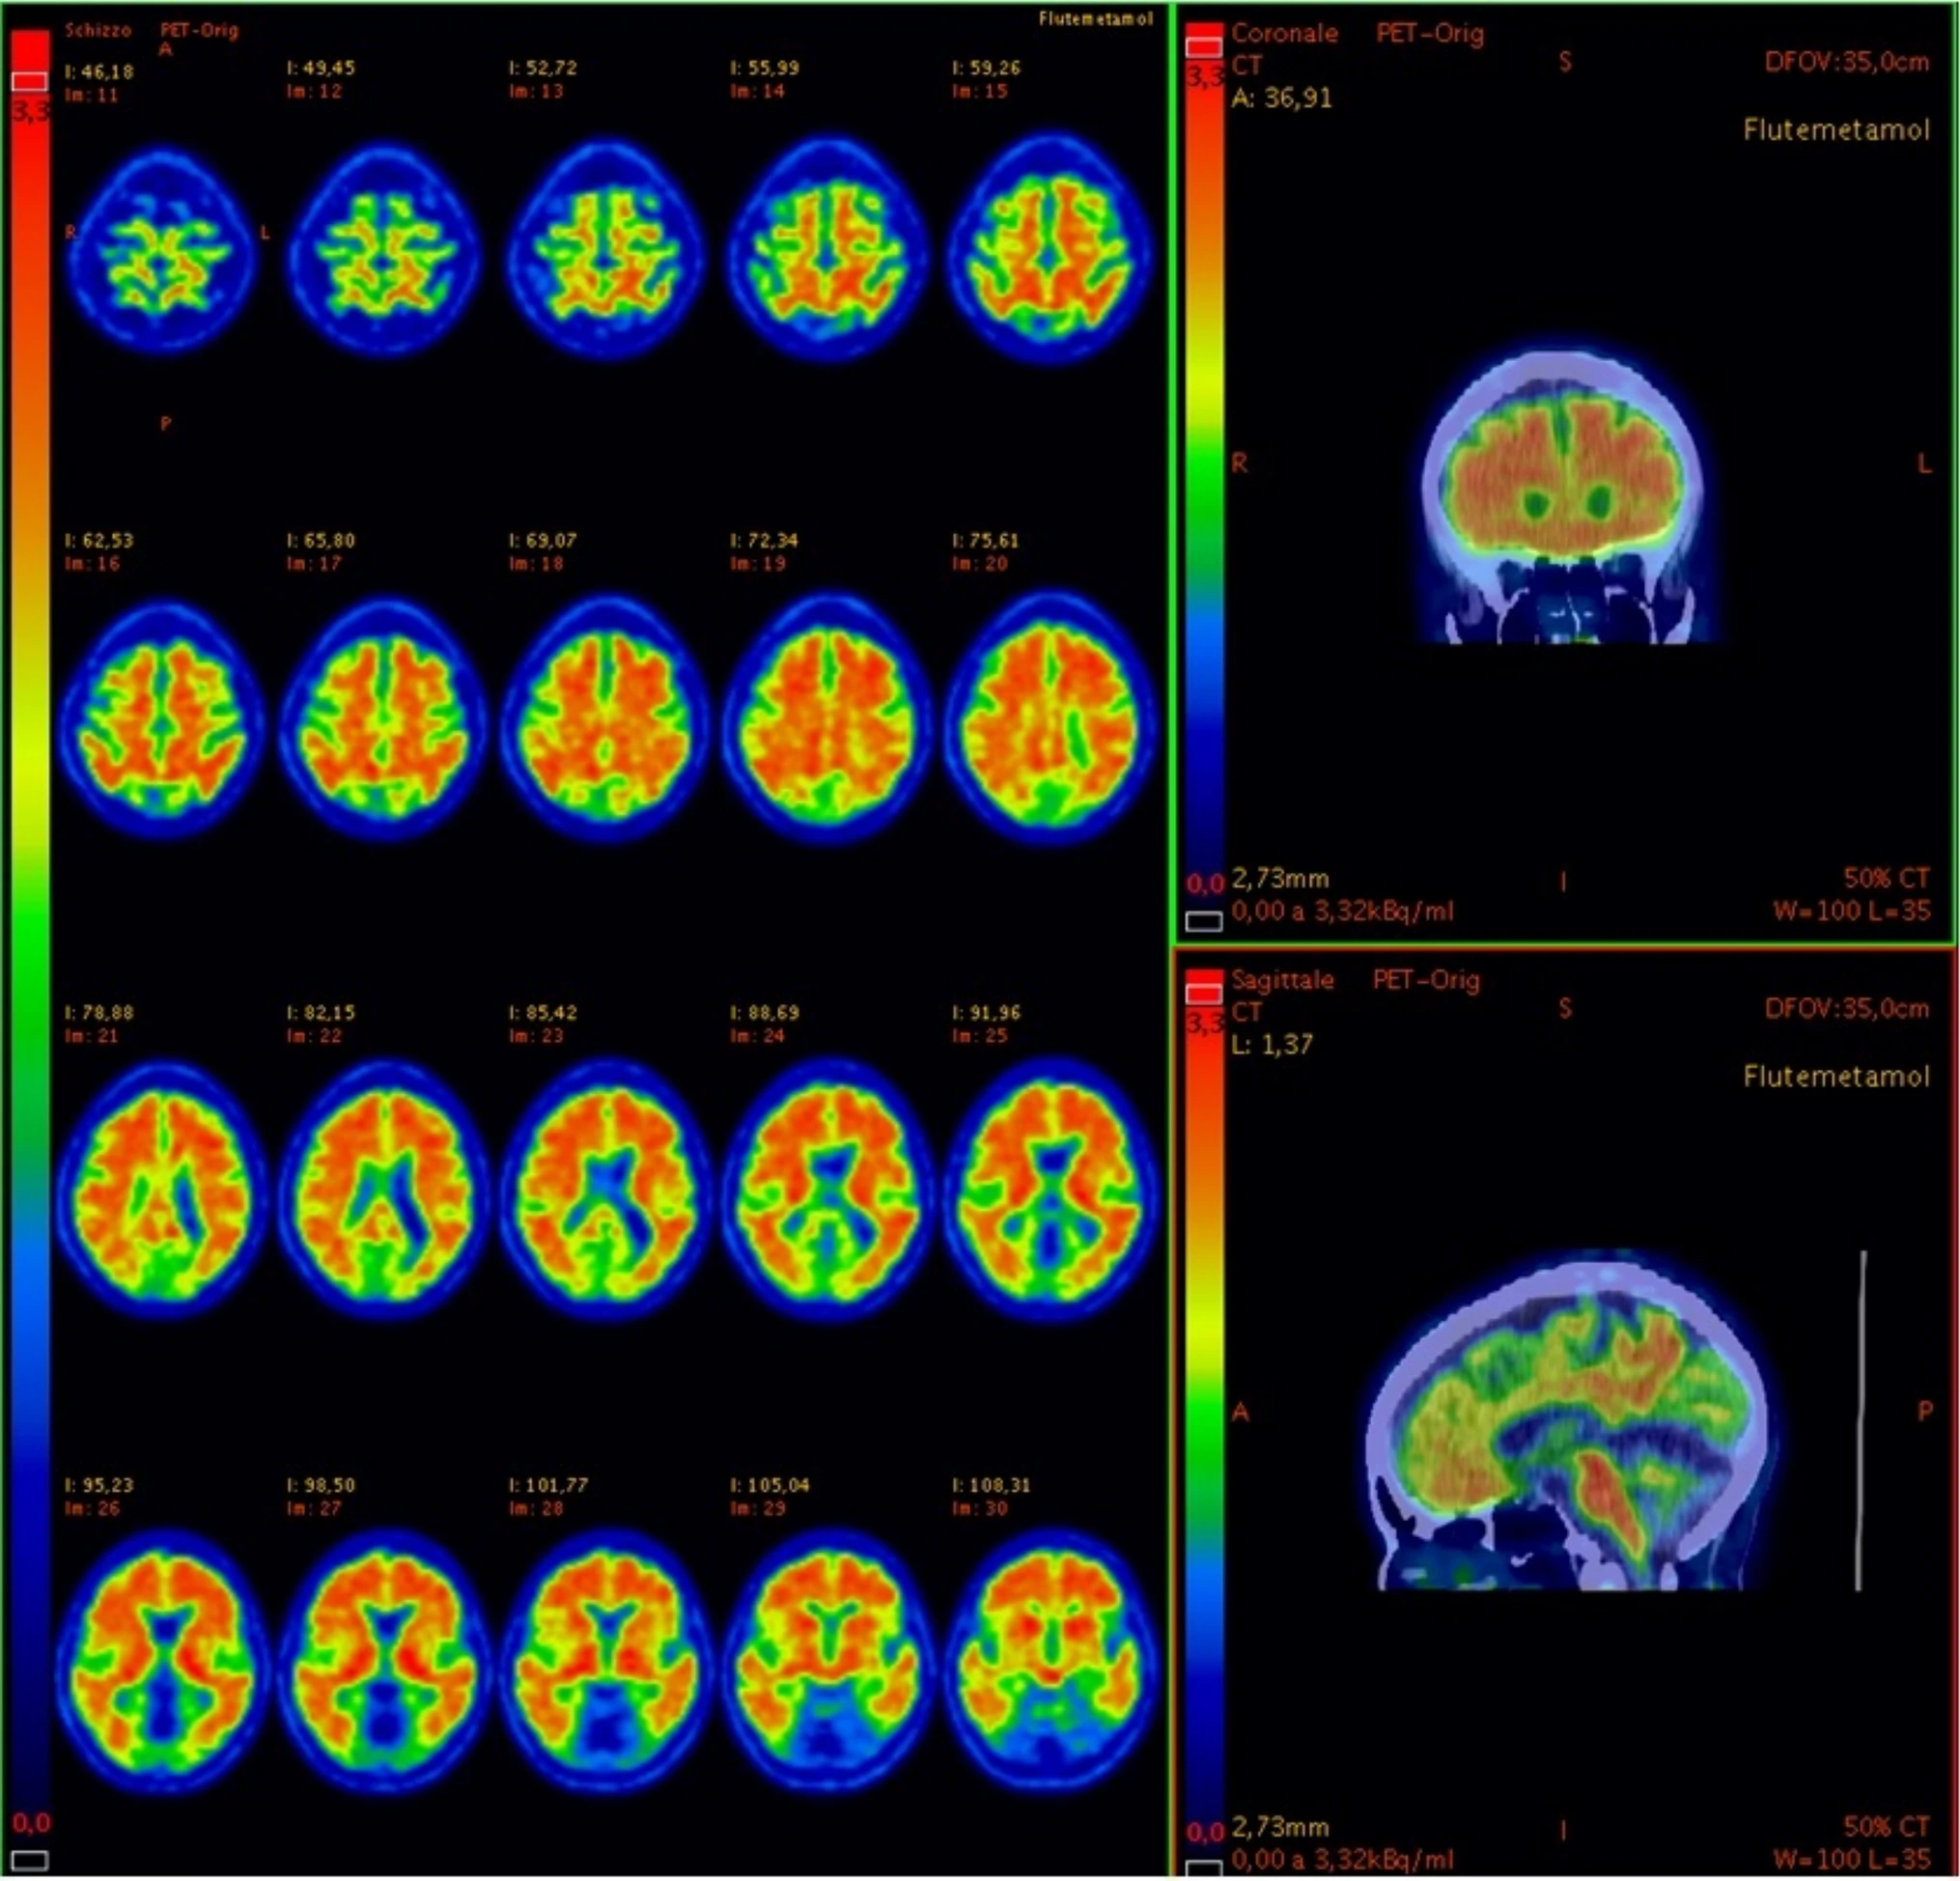

Al T1, 6/7 pazienti (86%) hanno mostrato una compromissione principale della memoria verbale, della velocità di elaborazione e dell’attenzione visiva; 5 pazienti su 7 (71%) hanno mostrato compromissione dell’apprendimento visuospaziale e 4 pazienti su 7 (57%) hanno ritardato il richiamo visuospaziale. I risultati suggeriscono che, oltre ai cambiamenti cognitivi, l’infezione da SarsCov-2 può anche indurre anomalie nel metabolismo cerebrale e possibilmente deposito di amiloide che persiste un anno dopo l’infezione. Le sequele neurologiche, compreso il deterioramento cognitivo che porta al morbo di Alzheimer, potrebbero in futuro essere una delle principali caratteristiche che complicano il COVID-19. “Ulteriori studi devono spiegare i meccanismi fisiopatologici alla base delle conseguenze neurologiche a lungo termine dell’infezione da SarsCov-2 e la sua possibile correlazione con il deterioramento cognitivo correlato all’amiloide. Da un punto di vista pratico, i medici dovrebbero sempre tenere a mente una storia di COVID-19 quando 18 F-FDG-PET rileva un ipometabolismo cerebrale focale o la PET/TC rivela una deposizione di amiloide altrimenti inspiegabile“ – hanno concluso gli scienziati.